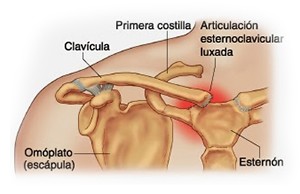

La clavícula es un hueso largo, con forma de "S" itálica, situado en la parte anterosuperior del tórax. Junto con la escápula forman la cintura escapular. Se puede palpar por toda su longitud y se extiende del esternón al acromion de la escápula, siguiendo una dirección oblicua lateral y posterior.

La clavícula es un hueso largo, con forma de "S" itálica, situado en la parte anterosuperior del tórax. Junto con la escápula forman la cintura escapular. Se puede palpar por toda su longitud y se extiende del esternón al acromion de la escápula, siguiendo una dirección oblicua lateral y posterior.

Se considera el único medio de unión entre el miembro superior y el tórax. A pesar de su aspecto, similar al de un hueso largo, posee una estructura semejante a la de un hueso plano, ya que carece de epífisis y de diáfisis, lo que la harían entrar dentro de la clasificación de hueso largo. Carece de un canal medular propiamente dicho.